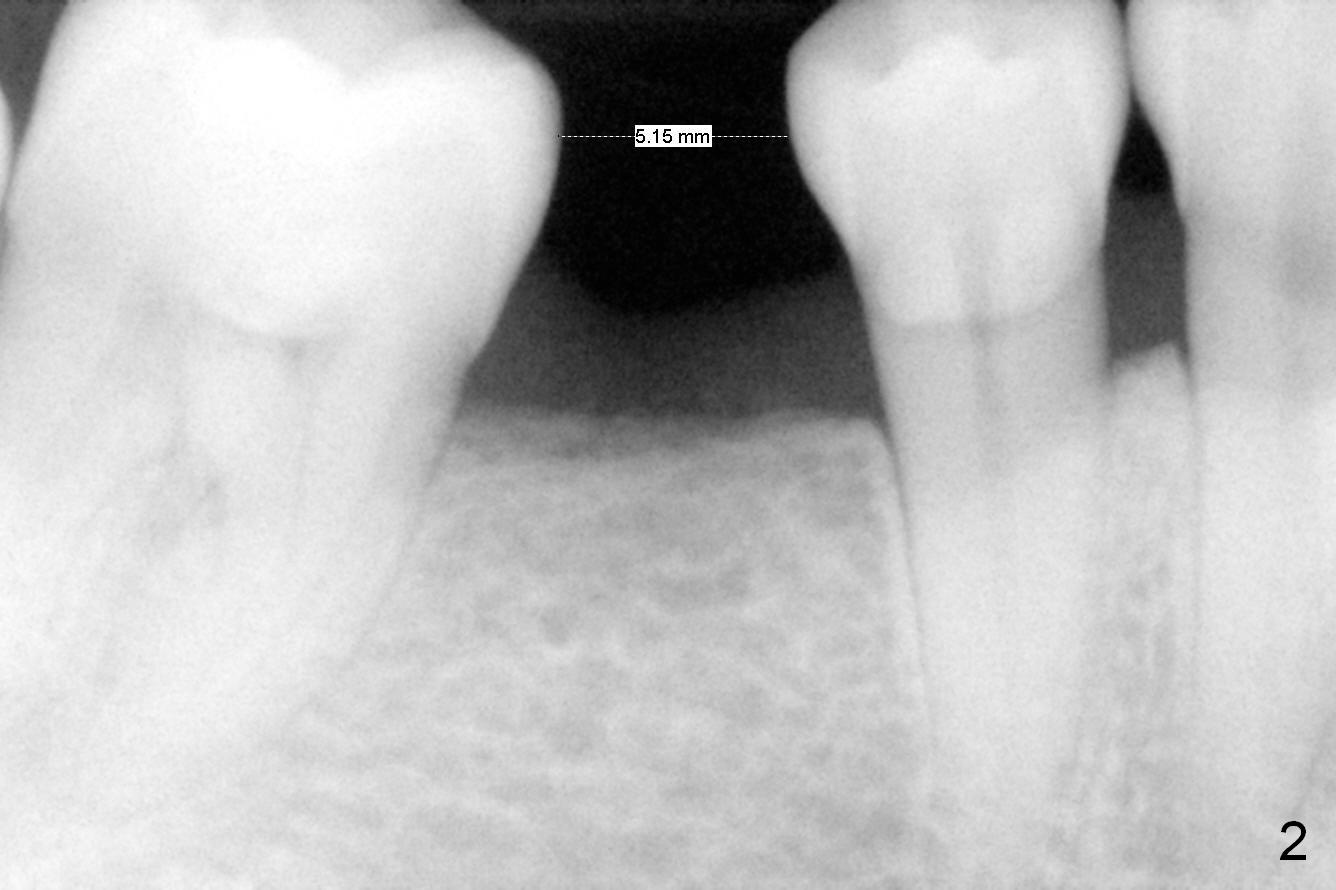

A 47-year-old lady has lost the lower right 1st molar for long time; with reduction of the buccolingual width (Fig.1) and mesiodistal width (Fig.2,3). With regional orthodontic appliance (Fig.4) for 3 months, the tooth #29 has started being distalized (Fig.5). One month and a half later, the tooth #26 starts to shift labially. Power chains and then closed coil spring are placed between #29 and 32. #29 distalization is slow (Fig.7) with closure of the diastema between #31 and 32 (Fig.8, as compared to Fig.1,3). Seven months post banding, a 10 mm miniimplant is placed distobuccal to the tooth #32 (Fig.6); the same 12-mm closed spring is stretched distal by ~ 6 mm (Fig.8 between arrowheads). Two months later, #29 is more distalized (Fig.9 tilted) with bone deposit mesially (*) and coronally (^). A .018' stainless steel wire is installed with an open coil spring placed between #28 and 29 (Fig.10 (^),11). Note #29 rotation (Fig.11). To solve the tilting, a power hook (Fig.12 black) will be clamped to a .016x.016 wire (red), while the closed spring is lowered and attached to the power hook (Fig.12 white). Take photos after removing the existing wire occlusally to show the alveolar width change. When the wire is placed, make sure that the distal wings of #29 bracket is fully engaged to reduce the tooth rotation. Make occlusal adjustment on #31 and 32 to reduce anterior open bite.